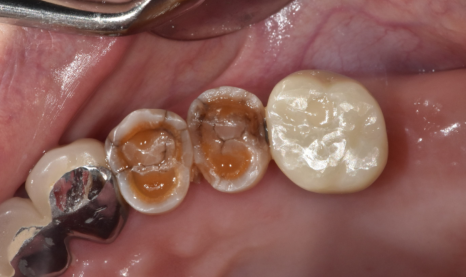

23.06.13

자연 치아 중에서도

많이 닳고 좋지는 않았지만

워낙 상실된 치아가 많아서

문제가 생기면 하나씩 치료하기로

상담해드리고..

23.06.21

23년 6월에 치료를 시작하시고

임플란트 치료 기간

얼마나 걸렸을까요?